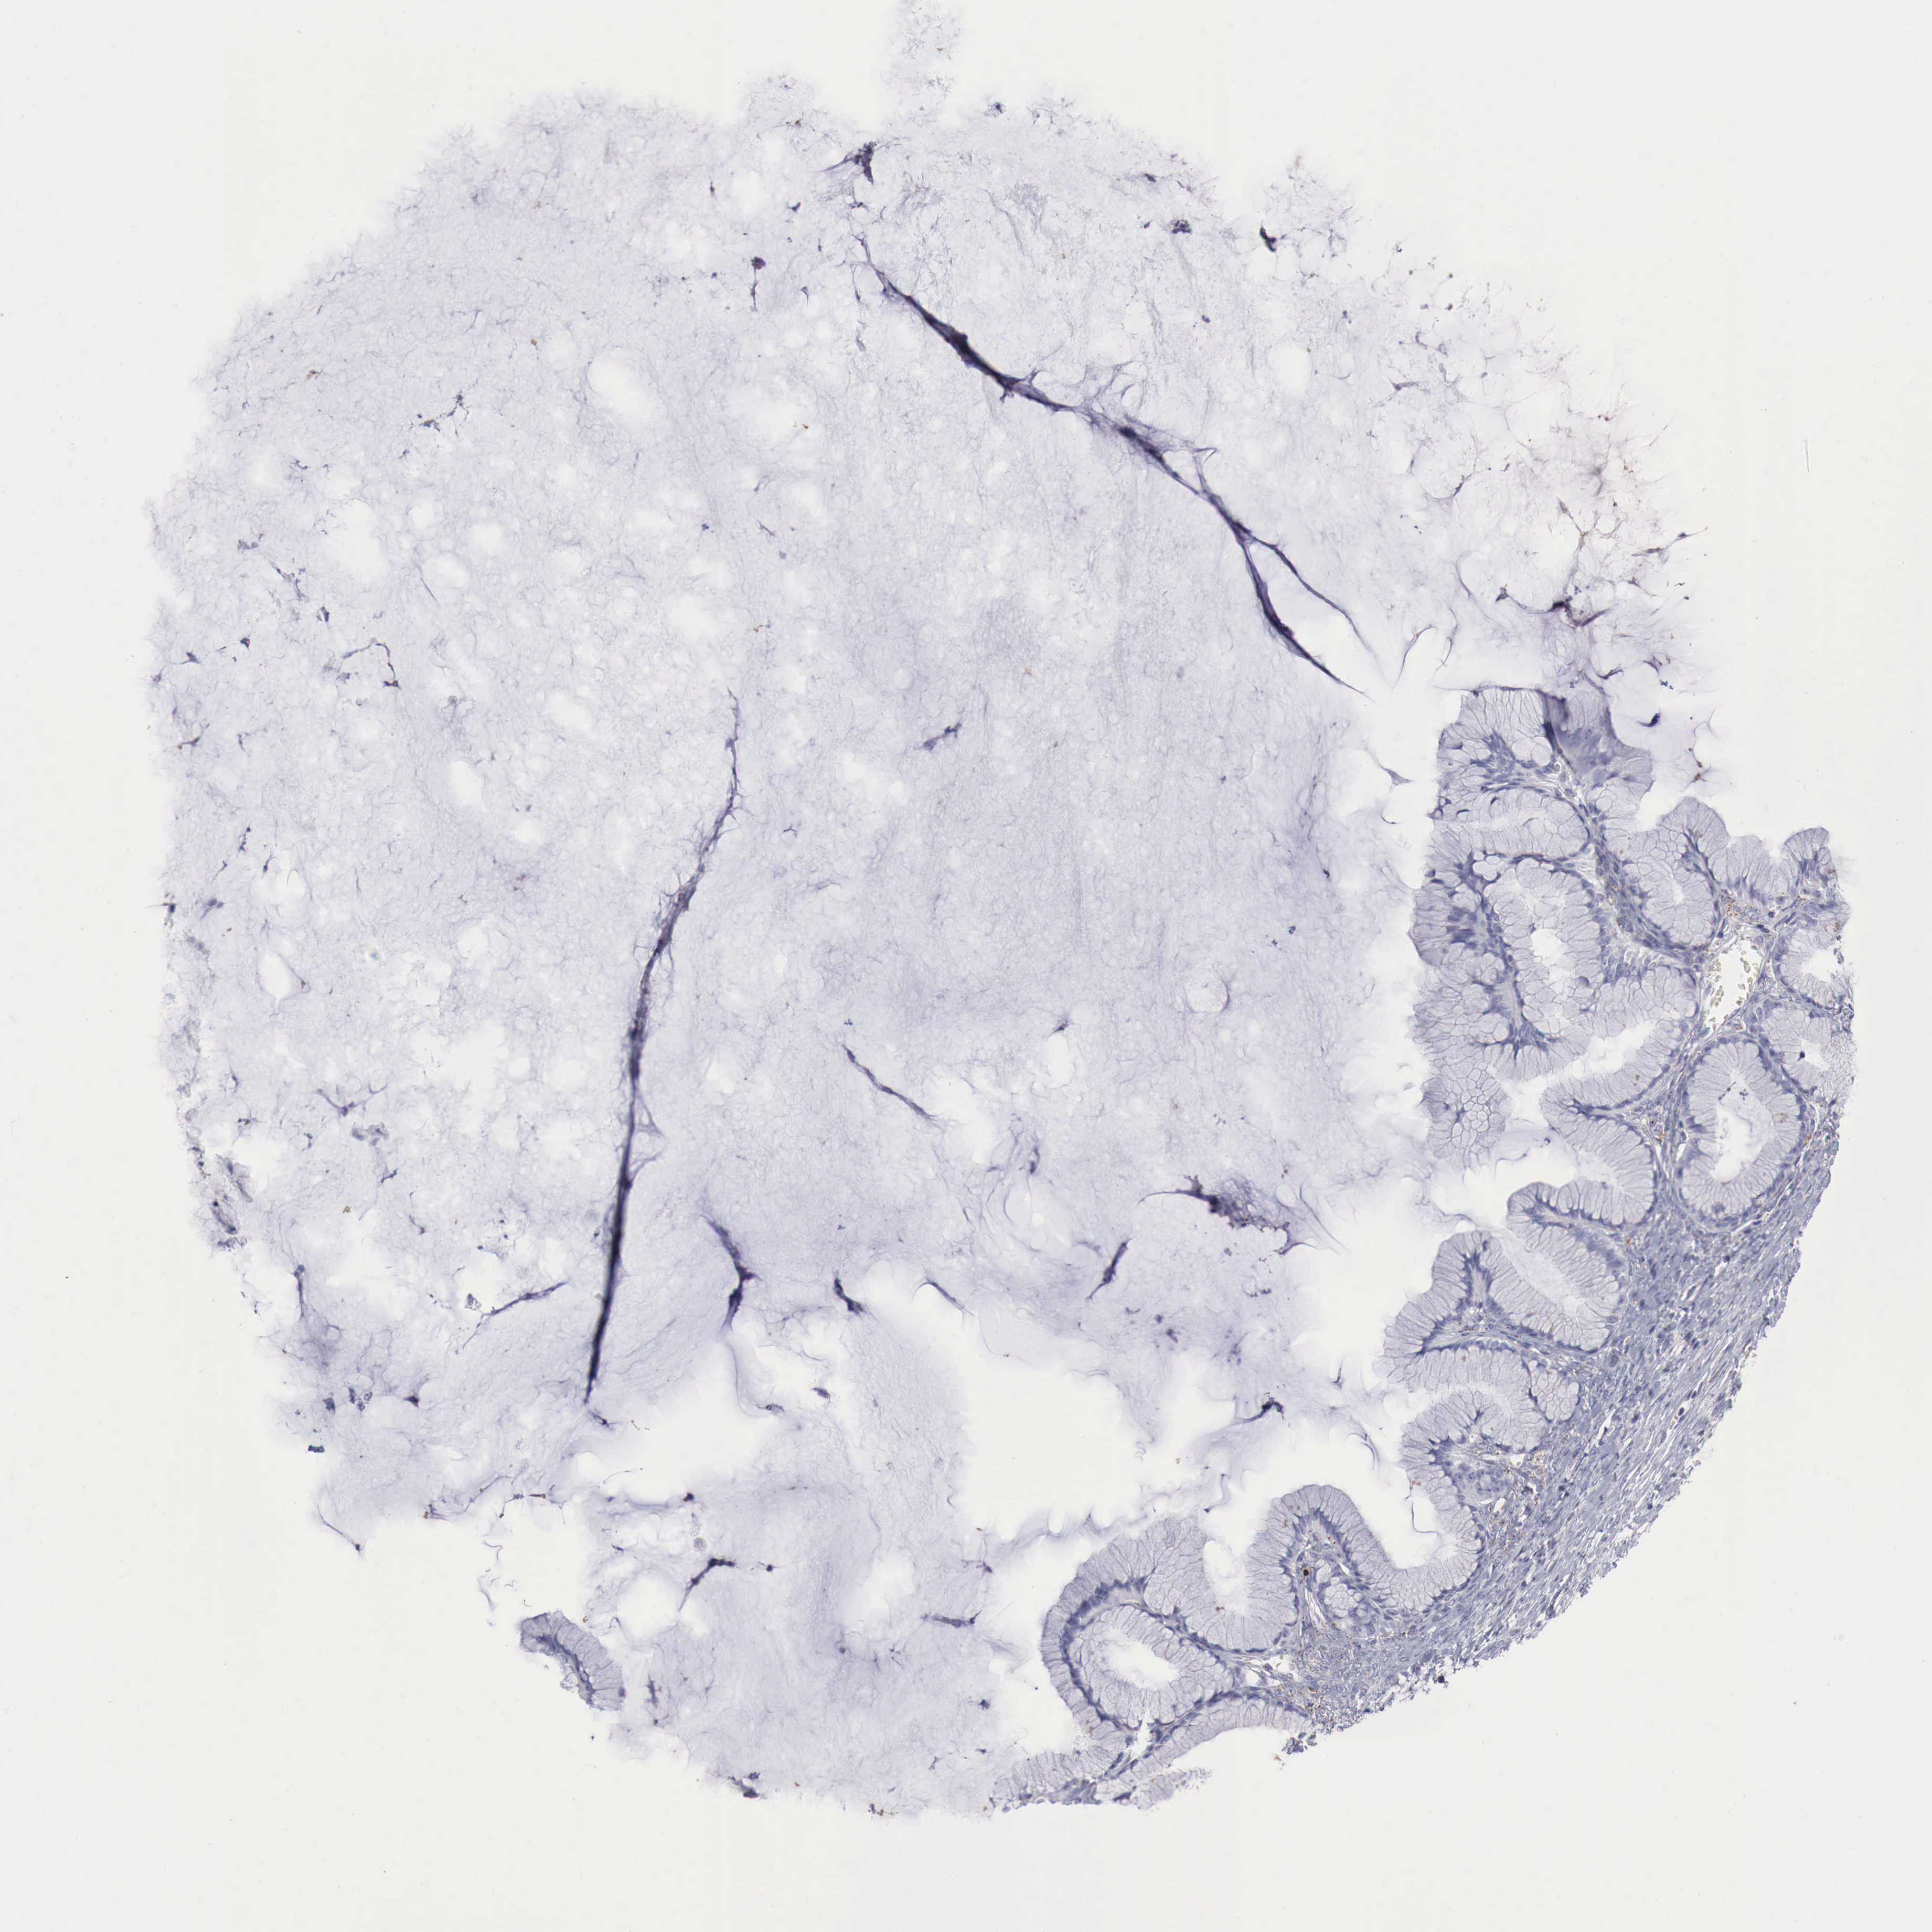

OVARIAN CANCER - Protein expressioni

A mouse-over function shows sample information and annotation data. Click on an image to view it in a full screen mode. Samples can be filtered based on level of antibody staining by selecting one or several of the following categories: high, medium, low and not detected. The assay and annotation is described here.

Note that samples used for immunohistochemistry by the Human Protein Atlas do not correspond to samples in the TCGA dataset.

Antibody stainingi

Antibody staining in the annotated cell types in the current human tissue is reported as not detected, low, medium, or high, based on conventional immunohistochemistry profiling in selected tissues. This score is based on the combination of the staining intensity and fraction of stained cells.

Each image is clickable and will lead to virtual microscopy that enables deeper exploration of all samples and also displays staining intensity scores, fraction scores and subcellular localization as well as patient and tissue information for each sample.

Antibody HPA000237

Antibody HPA000966

Cystadenocarcinoma, mucinous, NOS

Carcinoma, endometroid

Cystadenocarcinoma, serous, NOS